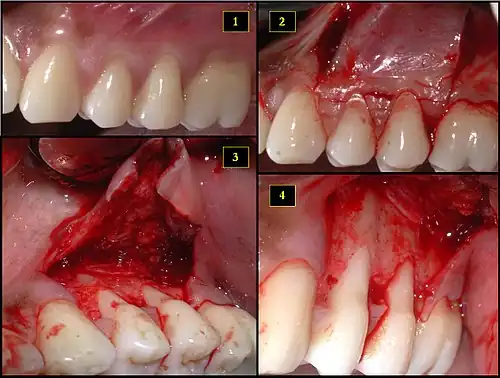

- Recipient site exhibits gingival recession on both premolars and first molar (molar recession is not an esthetic issue and will not be treated)

- Incisions prior to flap reflection

- Full thickness flap elevated

- Another viewpoint of the flapped recipient site